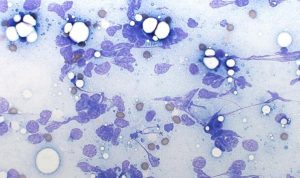

Figure 1. A very thick FNA smear. The preparation is too dense to allow reliable identification of individual cells.

Figure 2. A very thin FNA smear. Cellular yield is low, but the presence of surface lipid is noteworthy, as this may indicate a lipoma. Such smears may not fix well after air‑drying, and cells can be lost during staining.